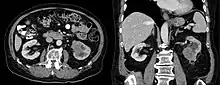

| Collecting duct carcinoma. H&E stain. | |

Histologic examination of collecting duct carcinoma demonstrates an infiltrative lesion with tubulopapillary, irregular channels lined by high grade hobnail cells with marked desmoplastic response and brisk neutrophilic infiltrate.